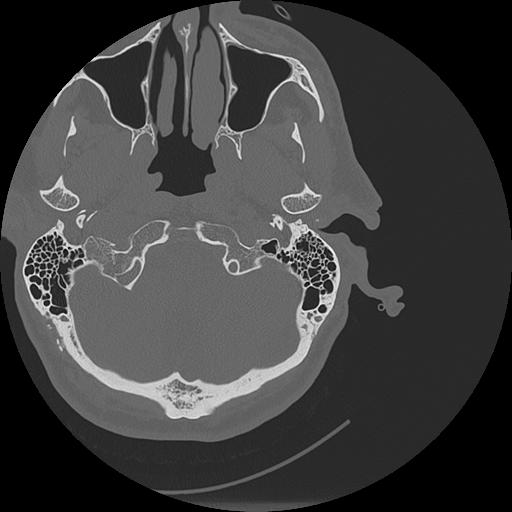

7 HUESO,,Vol,0.5,HUESO,,